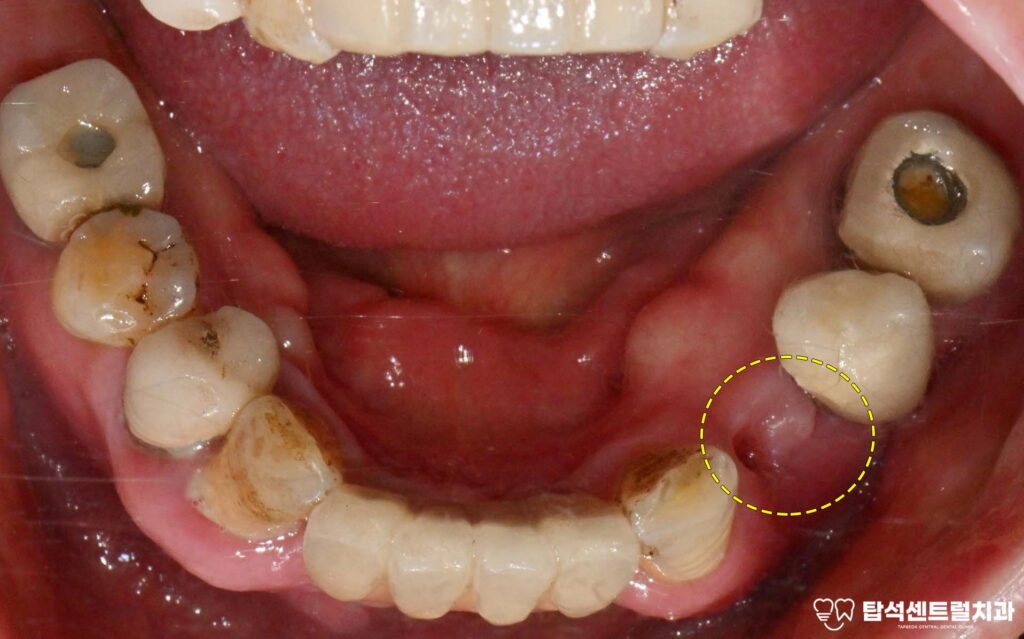

예를 들어 위턱 앞니 부위에 심은

브릿지 형태의 보철을 살펴보면

여러 개의 고정체가 연결되어 있어도

특정 부위에만 골소실이 집중될 수 있습니다.

한쪽은 상태가 양호하더라도 다른 쪽에

임플란트 주위염이 발생하면

해당 부위만 선택적으로 제거하고

새로운 치료 계획을 수립하게 됩니다.

이때, 결손되어 비어 있었던

아래 작은 어금니쪽에도

임플란트 하나를 같이 심어주었습니다.